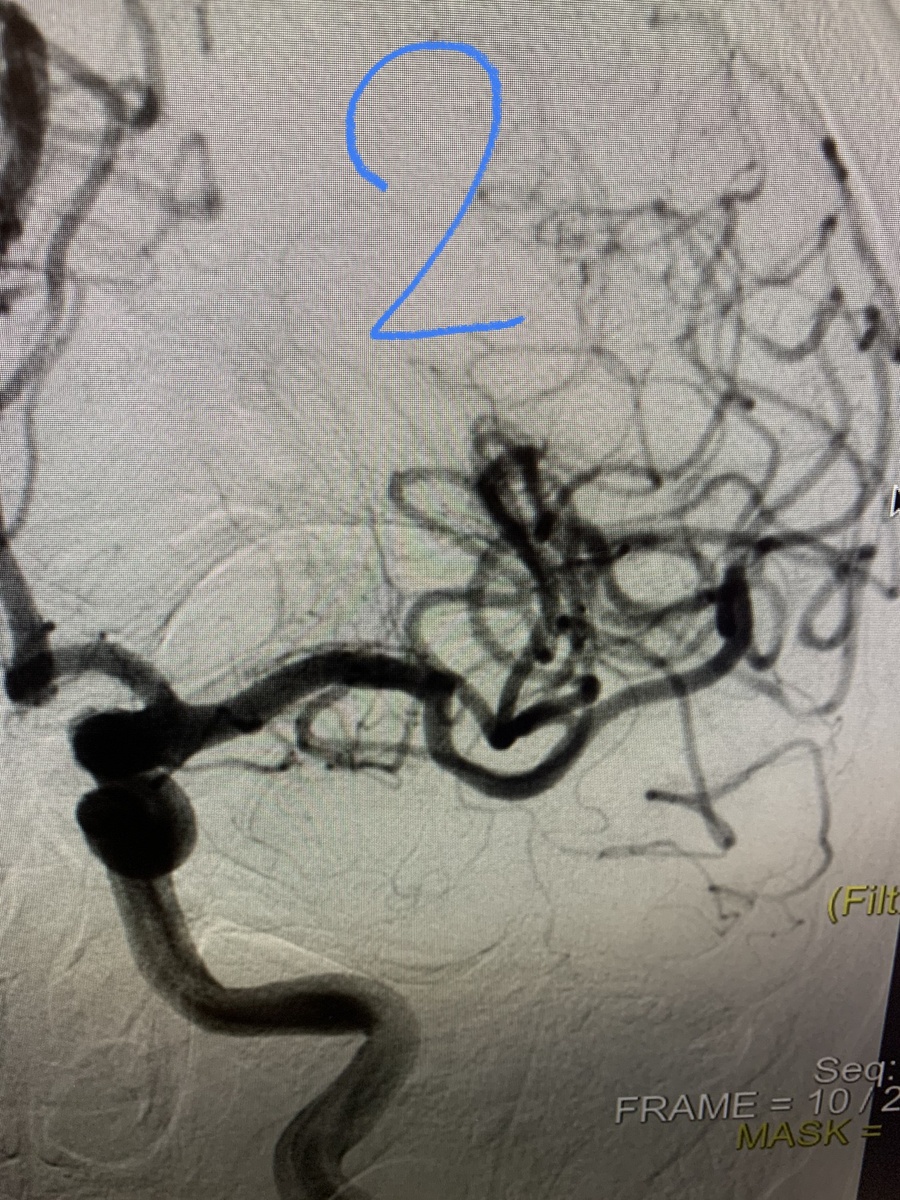

Говорят, что в этой группе одни ужасы и инфаркты. Поэтому вот вам история с инсультом и счастливым концом! В картинках, конечно. 1. Средняя мозговая артерия с тромбом. 2. А теперь она течет. 3. Аспирационный катетер Sofia, придуманный для заползания через все извитости внутренней сонной артерии далеко в голову.4. Тромб, который пытался превратить нашу пациентку в парализованного инвалида, но не смог. 5. Ольга Симонова - эндоваскулярный хирург, и анестезиолог Алексей Бельков, которые смогли в Елизаветинской больнице удалить тромб из средней мозговой артерии и вылечили пациентку с инсультом. Хотите чтоб Ольга с Софией забралась и в Вашу среднюю мозговую? тогда есть 3 совета: 1. Никаких статинов с высоким холестерином. 2. Высокое давление - дело житейское и таблеток не требует. А главное: 3. при мерцательной аритмии не принимать антикоагулянты. Будьте здоровы и берегите себя! PS и пожалуйста, знайте симптомы инсульта